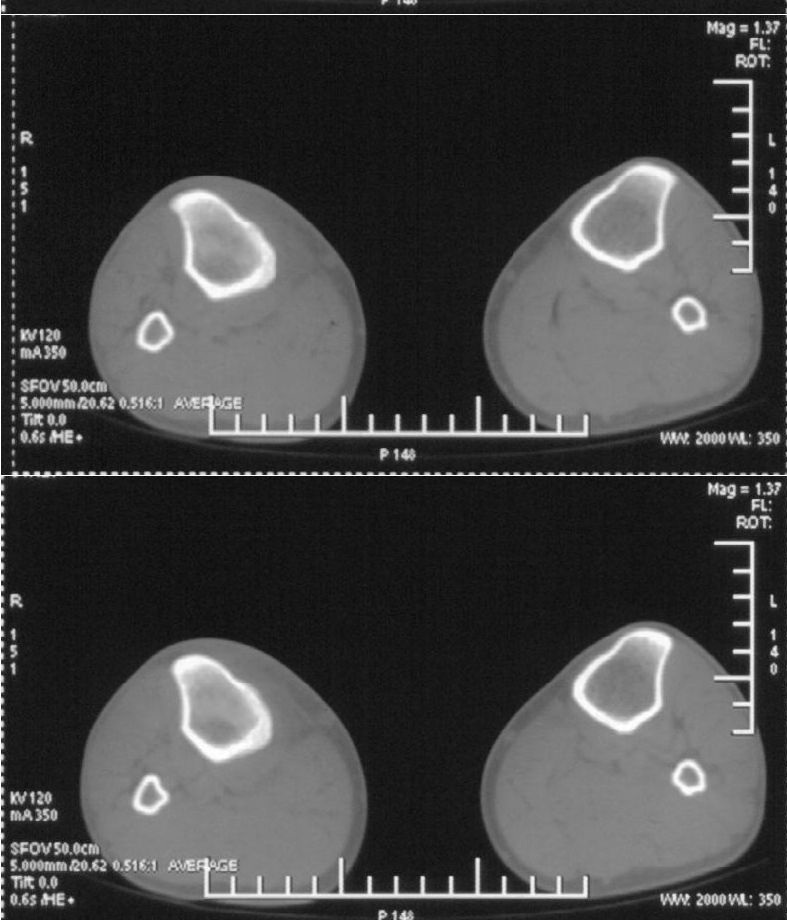

男,42岁。4个月前钢筋钝伤右侧小腿部,当时因无明显外伤,未引起重视。一周后因受伤腿部疼痛,发现肿胀,随后到当地医院进行检查(2008年4月16日)。因未发现骨质异常未引起重视,仅仅进行口服抗生素治疗处理。经过一段时间治疗但未见明显治疗效果在5月29日又进行x线检查,发现有胫骨密度上段密度增高,又进行抗炎治疗,仍未见效果。又在7月3日进行x线检查,仍然报告有胫骨上端密度增高,并建议ct检查。以下是相关检查结果:

髓腔密度呈絮状增高,胫骨上端内侧可见层状骨膜反应,考虑骨髓炎.

髓腔密度呈絮状增高,胫骨上端内侧可见层状骨膜反应,肌间隙模糊,考虑骨髓炎.